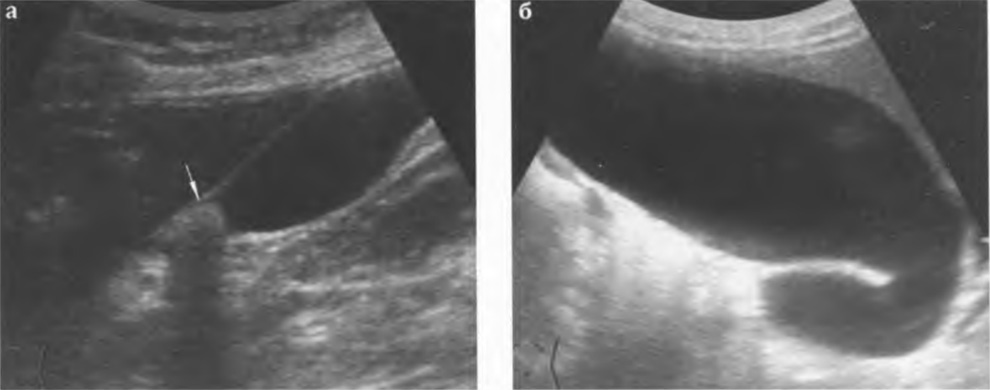

Водянка. Возникает при нарушении оттока желчи из полости желчного пузыря, что наиболее часто связано с ущемлением камня в области его шейки или с препятствием в области холедоха (опухоль, холедохолитиаз) и развитием желчной гипертензии. При этом размеры пузыря значительно увеличиваются (> 0,9-1,0 см), в просвете, вследствие нарушения реологических свойств желчи, появляется осадок. Стенка в области тела желчного пузыря обычной толщины (рис. 3.10 а, б).

Рис. 3.10 а,б. Водянка желчного пузыря: а - желчный пузырь увеличен в размерах, стенка истончена, средней эхогенности, в области шейки лоцируется конкремент (стрелка); б - значительно растянутый желчный пузырь при желчной гипертензии; блок на уровне дистального отдела холедоха.